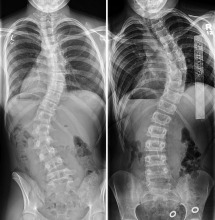

Σκολίωση - Schroth

Η Schroth method είναι μέθοδος αντιμετώπισης της σκολίωσης, κύφωσης και της λόρδωσης για ανθρώπους όλων των ηλικιών, είναι επισήμως αναγνωρισμένη από τις διεθνείς επιστημονικές κοινότητες Scoliosis Research Society (SRS) και Society On Scoliosis Orthopaedic and Rehabilitation Treatment (SOSORT), που χρησιμοποιεί ειδικές εξατομικευμένες ασκήσεις προσαρμοσμένες στον τύπο της σκολίωσης.

Βασίζεται στην τρισδιάστατη αυτο-διόρθωση της σκολιωτικής στάσης, στην επιμήκυνση της σπονδυλικής στήλης , στην εφαρμογή της στροφικής αναπνοής και στην εκπαίδευση διατήρησης των διορθώσεων κατά τις καθημερινές δραστηριότητες